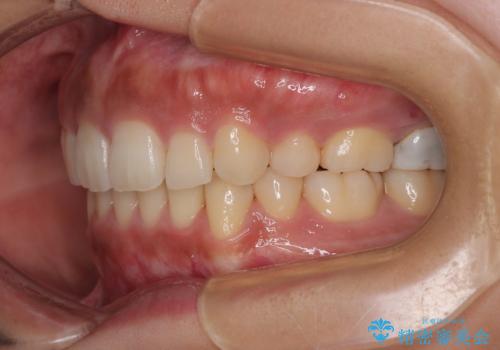

- 前歯のデコボコと口元の突出感を気にして来院された患者様です。

上下前歯がくちばしのように突出していたため、上下左右の第一小臼歯4本を抜歯し、ワイヤー装置にて矯正治療を行うこととしました。

口元の突出感が改善されてことで、下唇に引っかかっていた上顎前歯も気にならなくなりました。